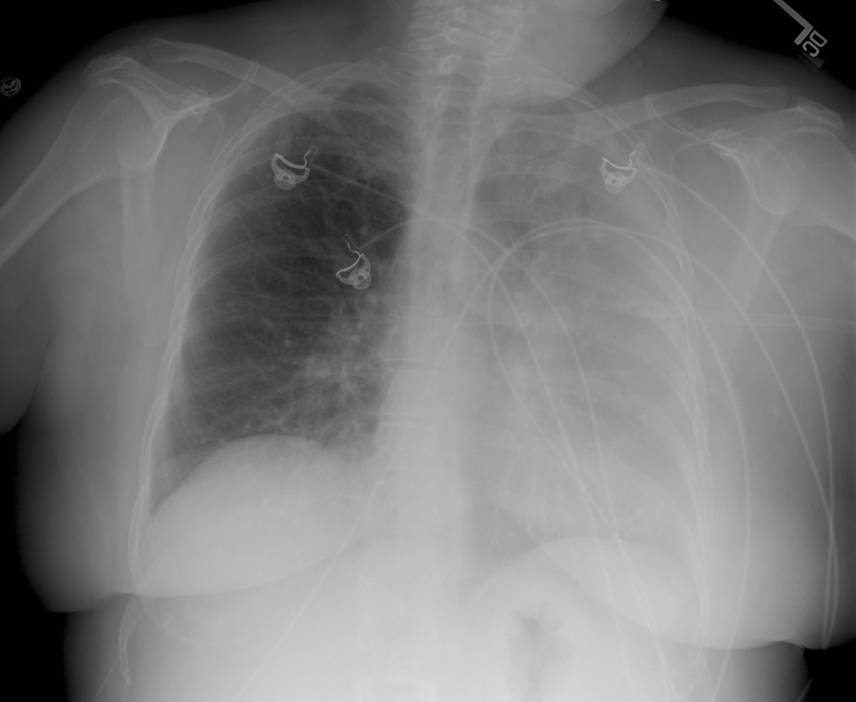

She presented to an outside hospital emergency department and was found to have an abnormal chest x-ray. Posterior-anterior (PA) and lateral films were provided (Figures 1 and 2).

Figure 1. Posterior-anterior chest x-ray demonstrating left sided consolidation without volume loss.